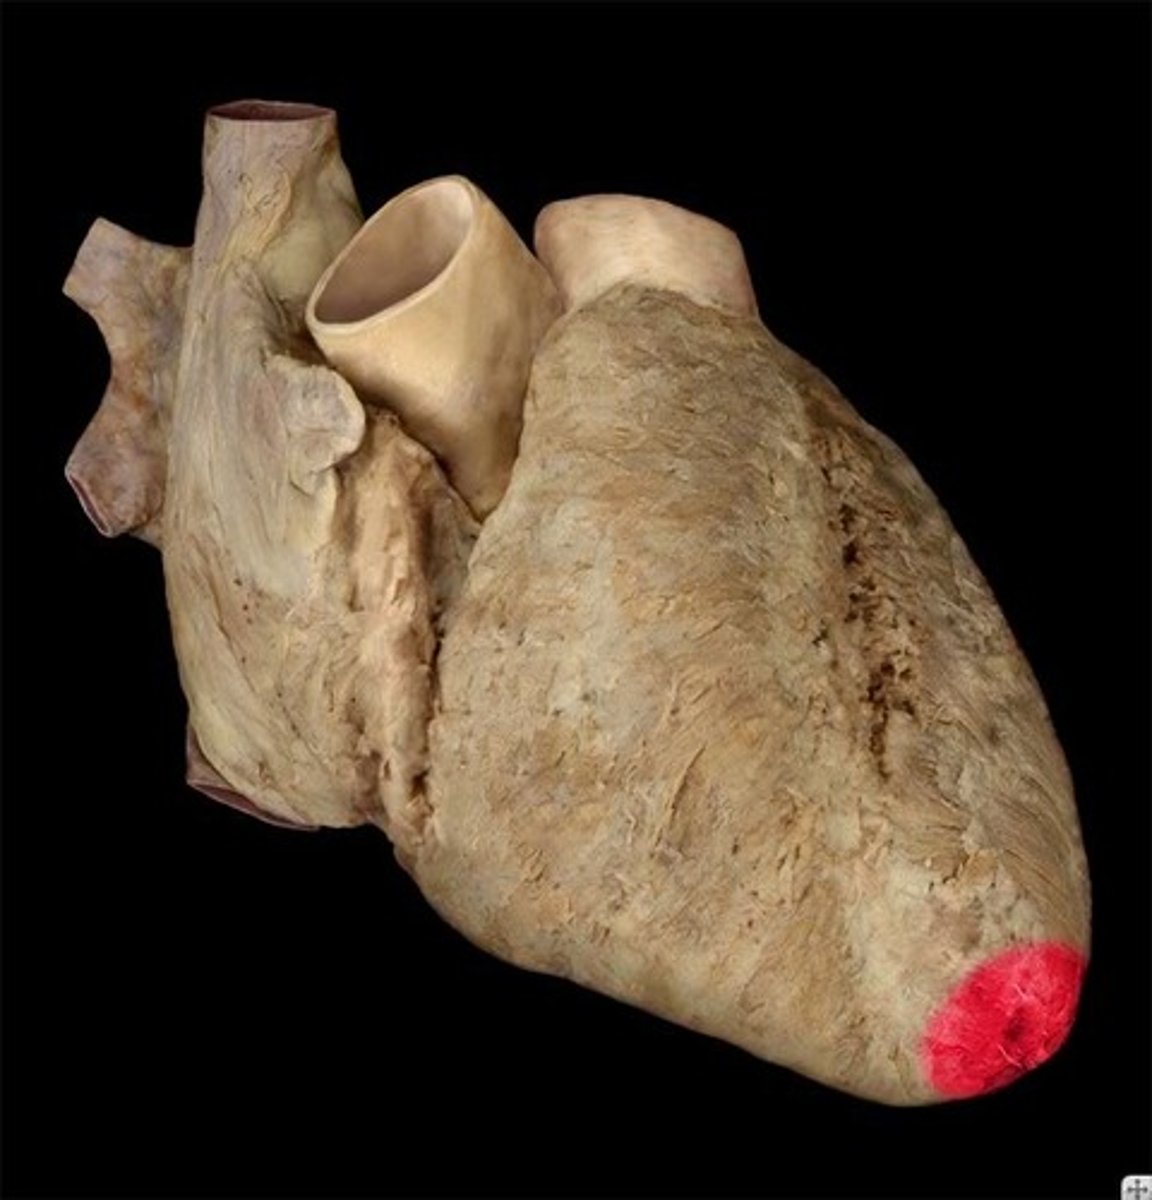

apex